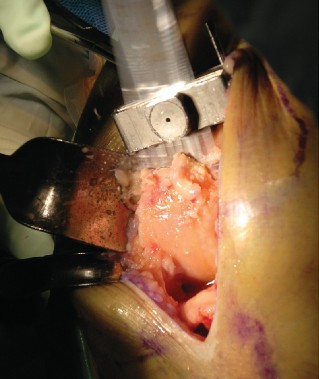

The most ubiquitous approach for TKA is the medial parapatellar arthrotomy. A straight, anterior longitudinal skin incision is made, extending from just proximal to the superior pole of the patella to just medial to the tibial tubercle. Full-thickness fasciocutaneous flaps are elevated to preserve the subdermal vascular plexus. The arthrotomy is then initiated through the medial retinaculum, coursing proximally into the quadriceps tendon (leaving a small medial cuff for later repair) and distally along the medial border of the patella and patellar tendon.

Once the joint is entered, the patella is either everted laterally or laterally subluxated, depending on the surgeon's preference and the stiffness of the extensor mechanism. A meticulous synovectomy and excision of the infrapatellar fat pad (Hoffa's fat pad) are performed to enhance visualization of the lateral compartment and the tibial plateau. All peripheral osteophytes on the femur and tibia must be aggressively resected at this stage. Retained osteophytes will artificially tension the collateral ligaments, leading to erroneous gap balancing and postoperative stiffness.

Bony Resection and Gap Balancing

The philosophy of TKA relies on creating equal and symmetrical flexion and extension gaps. This can be achieved via a "measured resection" technique (resecting bone equal to the thickness of the implant based on anatomical landmarks) or a "gap balancing" technique (tensioning the soft tissues first and making bone cuts parallel to the tensioned ligaments). Most modern surgeons utilize a hybrid approach.

The distal femoral resection is typically performed first, utilizing an intramedullary alignment guide. The entry hole is made just anterior to the origin of the PCL. The valgus angle of the cutting block is set based on preoperative templating (usually 5 to 7 degrees) to restore a neutral mechanical axis. The distal cut removes approximately 9 mm of bone from the most prominent condyle, corresponding to the thickness of the femoral component.

Next, the proximal tibial resection is executed, almost exclusively using an extramedullary alignment guide. The guide is aligned with the medial third of the tibial tubercle proximally and the center of the talus distally. The cutting block is set to resect 8 to 10 mm of bone from the unaffected compartment, incorporating a 3 to 5-degree posterior slope. This cut must be strictly orthogonal to the mechanical axis of the tibia in the coronal plane.

Femoral sizing and rotation are then determined. Proper femoral rotation is paramount for patellofemoral tracking and flexion gap symmetry. The rotation is typically set at 3 degrees of external rotation relative to the posterior condylar axis (PCA), or parallel to the surgical transepicondylar axis (TEA) and perpendicular to Whiteside's line (the AP axis of the trochlea). Once rotation is established, the anterior, posterior, and chamfer cuts are made using a 4-in-1 cutting block.